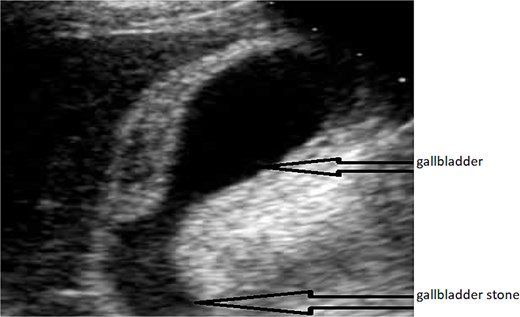

Abdominal ultrasound: A distended gallbladder with thickened walls and visible gallstones, typical of acute cholecystitis (Fig. 1).